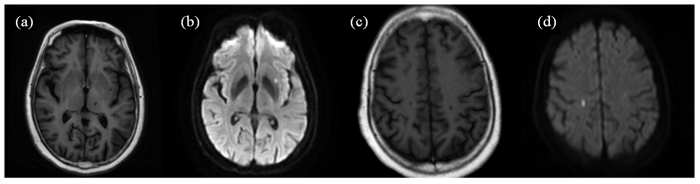

一位单发急性脑梗塞复发患者磁共振轴位SE T1WI (a、c)、DWI (b、d)图像. 患者首次住院,行磁共振检查显示,左侧外囊单发腔梗呈长T1信号(a),DWI弥散受限呈高信号(b);患者康复出院后4个月出现临床症状,行磁共振检查显示,右侧顶叶单发腔梗灶,呈长T1信号(c),DWI扩散受限呈高信号(d)

Fig. 2

Magnetic resonance axial SE T1WI (Fig. a, c) and DWI (Fig. b, d) of a patient with recurrent single lesion of acute stroke.The patient was admitted to the hospital for the first time, and an MRI showed a single lumen infarction in the left external capsule with a long T1 signal (Fig. a) and diffusion-limited DWI with a high signal (Fig. b). The patient developed clinical symptoms four months after discharge from rehabilitation, an MRI showed a single lumen infarction in the right parietal lobe with a long T1 signal (Fig. c) and diffusion-limited DWI with a high signal (Fig. d)